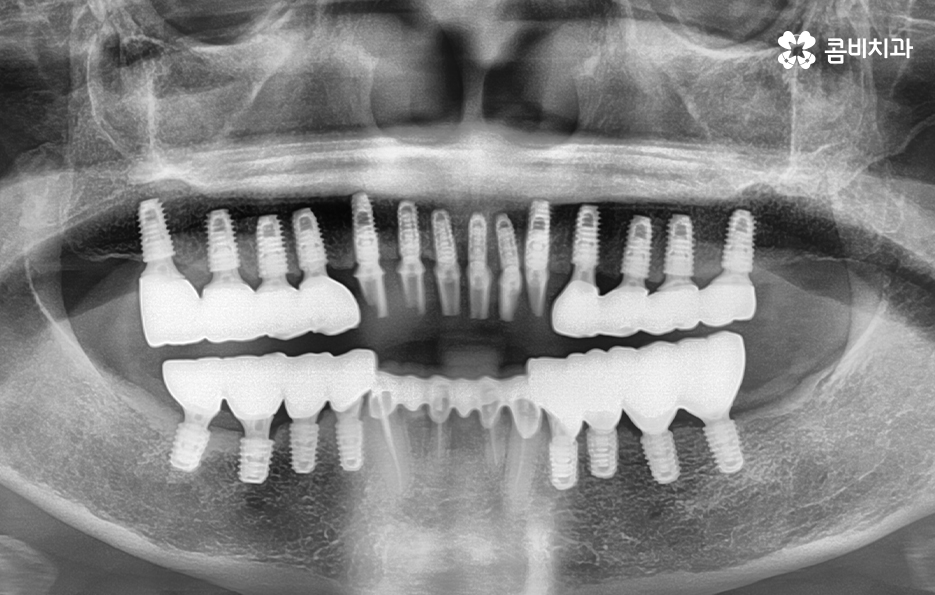

임플란트의 기본적인 원리는 잇몸뼈(치조골)에 식립을 하여

단단하게 고정이 된 상태에서 보철물을 씌워

자연치아와 비슷한 역할을 하게 되는 것인데

이때 가장 중요한 부분이 치조골에 얼마나 건강하고

단단하게 고정이 되느냐입니다.

보철물의 경우에는 손상이 되면 교체가 가능하지만

잇몸뼈의 손상으로 인해서 재수술을 하게 될 경우

성공율이 점점 떨어질 수밖에 없기 때문에

처음 치료를 할 때 건강하게 마무리를 하고

부작용이 발생하지 않도록 주의사항을 잘 지켜야 합니다.

기존 치아의 색과 모양에 어울리는 보철물을 씌워서 마무리하는 과정